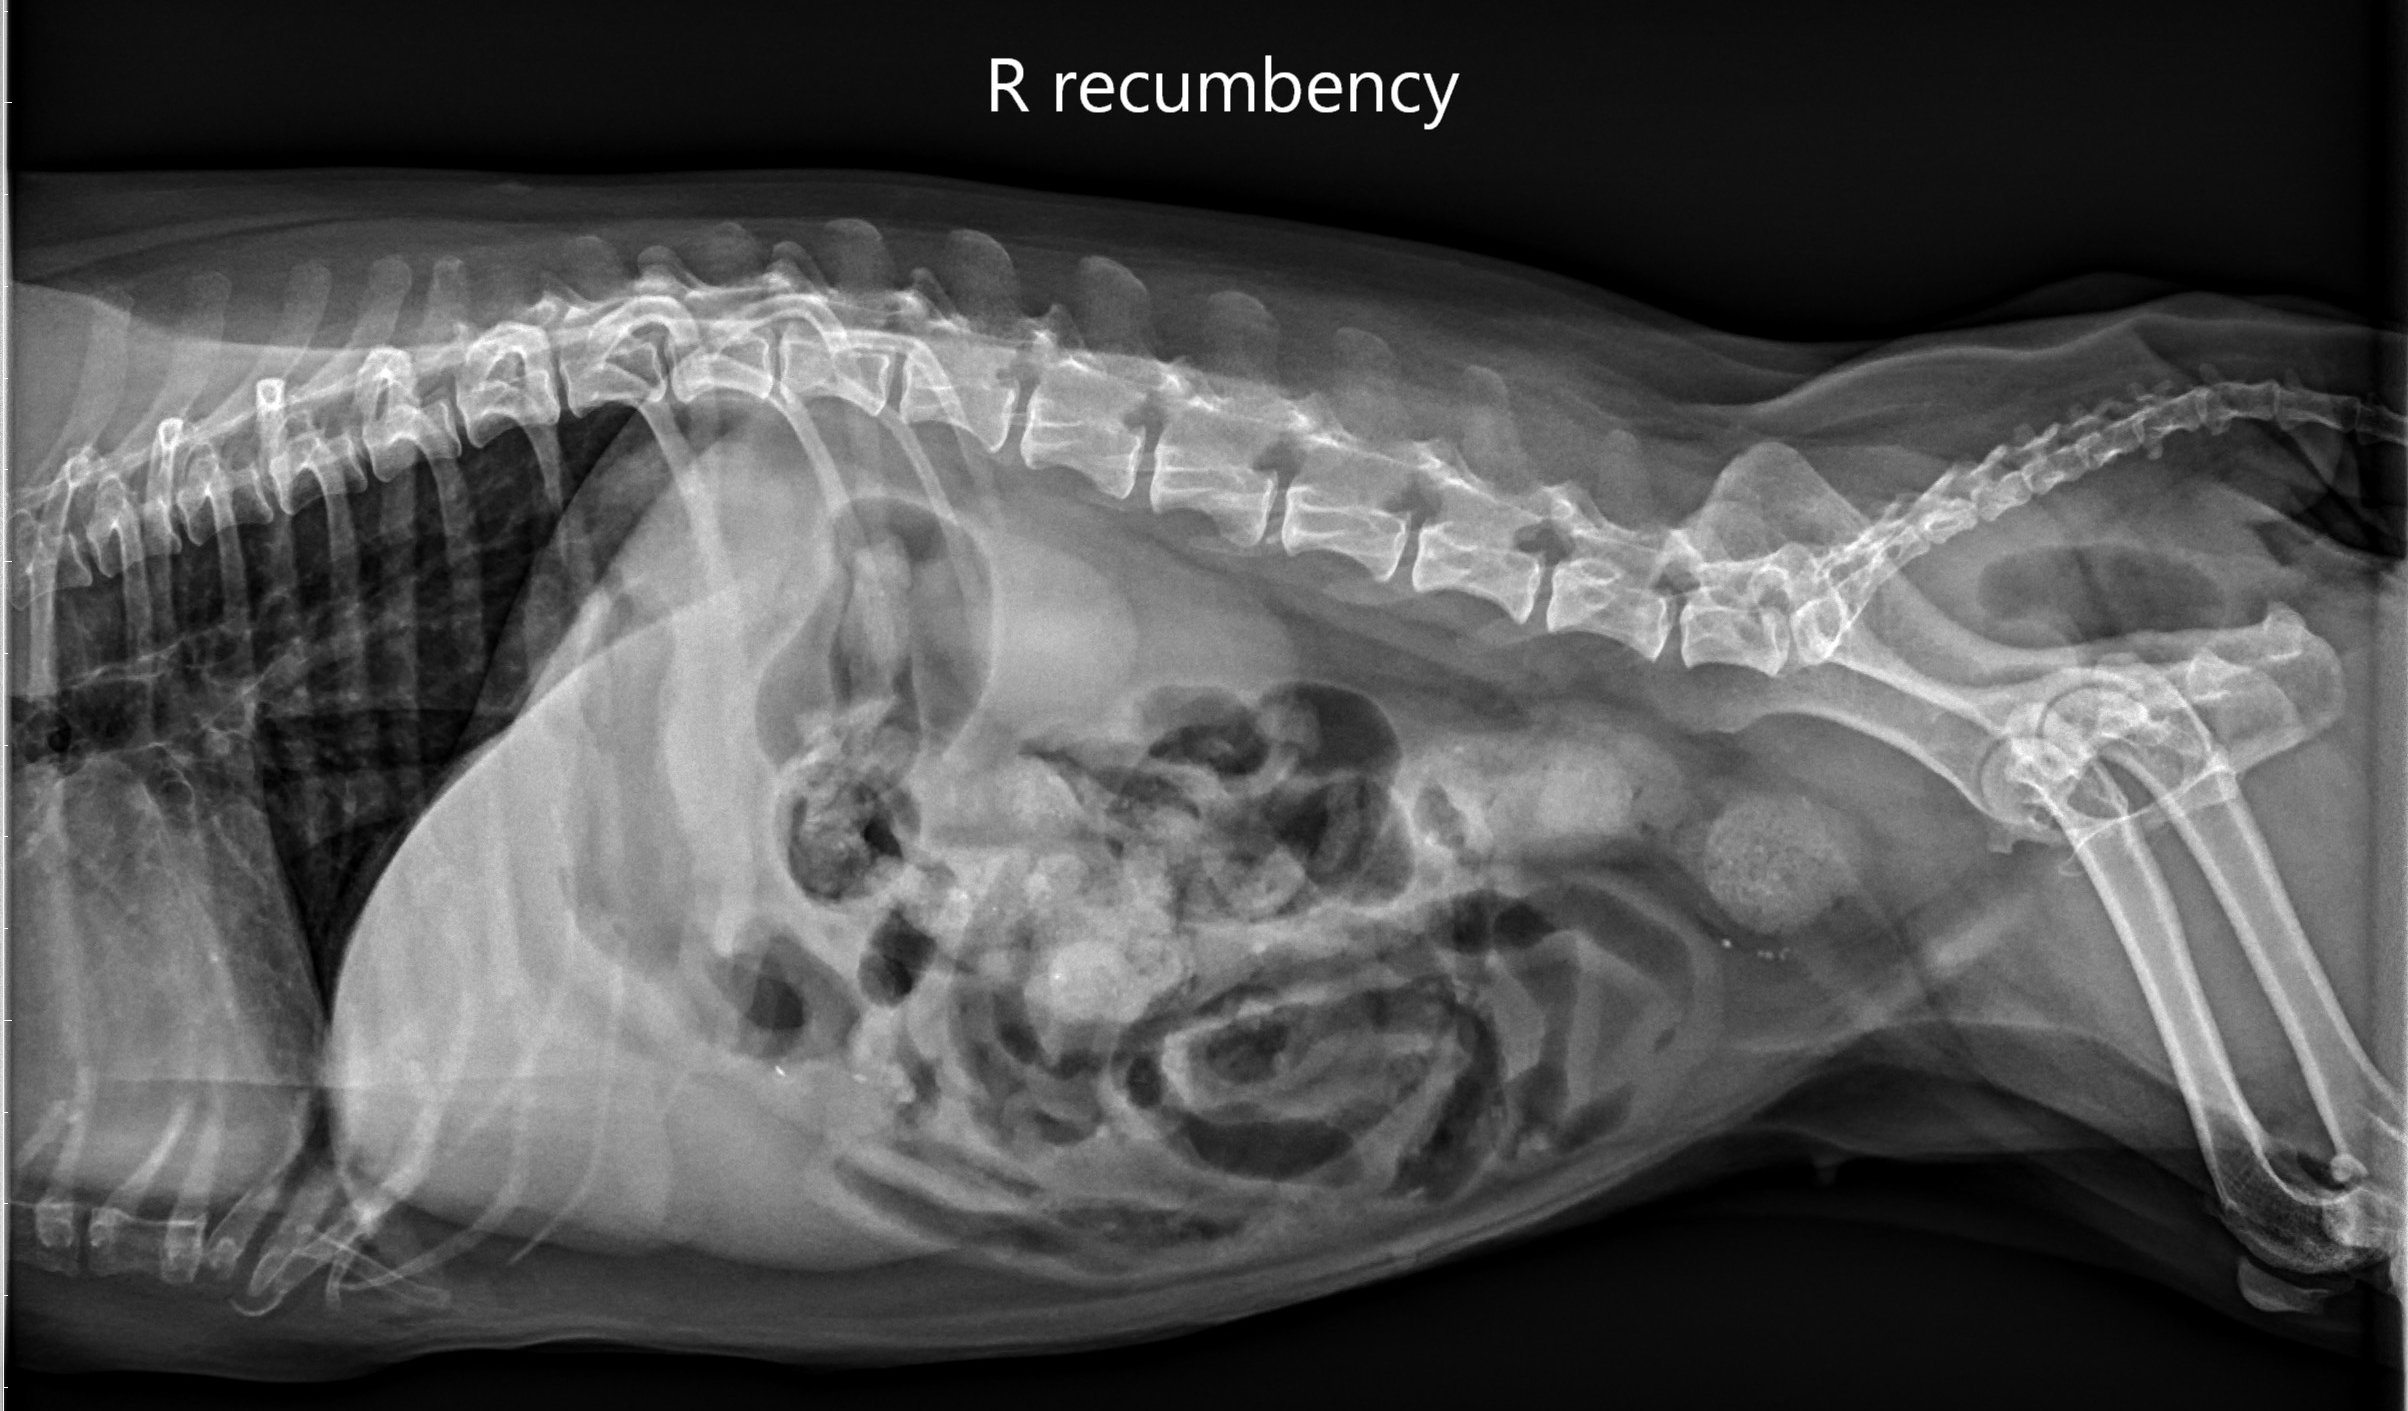

術前x光片,後腹腔白色團塊為無法順利排出的糞便,骨盆內的腸道嚴重狹窄。

這次的手術是將腸道支架由肛門置入,在連續X光透視下,導引支架在腸腔內自動展開,提供一個持續性360度的張力,能有效撐開狹窄區,恢復腸道的通暢。由於是無創的手術,病患不須接受深度的麻醉,且操作時間很短,包含內視鏡檢查大約只需要30分鐘,因此也可大幅減少麻醉時間,對於末期腸癌的病患來說身體負擔較小。